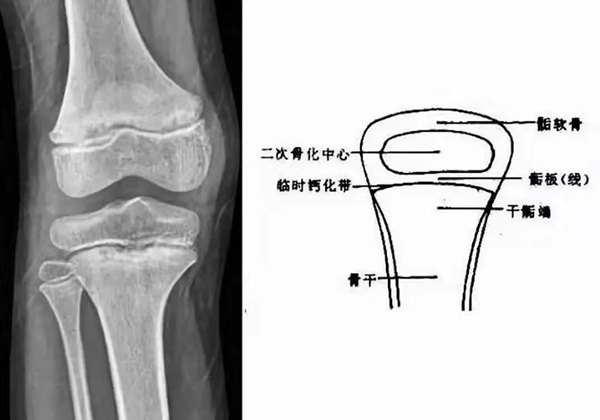

我們都知道,人體的高矮是由骨骼的生長發(fā)育決定的,特別是下肢長骨。長骨呈長管狀,在長骨的兩端有一種專管骨骼生長的骺軟骨,它與干骺端之間有一盤狀軟骨結(jié)構(gòu)稱為骺板(線),在幼兒的X光片上表現(xiàn)為一條較寬的透光帶。 (見下圖)

未成年時隨著年齡的增加骺軟骨端不斷骨化,骨骼就不斷增長。當(dāng)骨骺線完全閉合時骨骼就停止生長,個子也就不再增長了。一般骨骺端完全閉合的年齡是18~20歲左右。